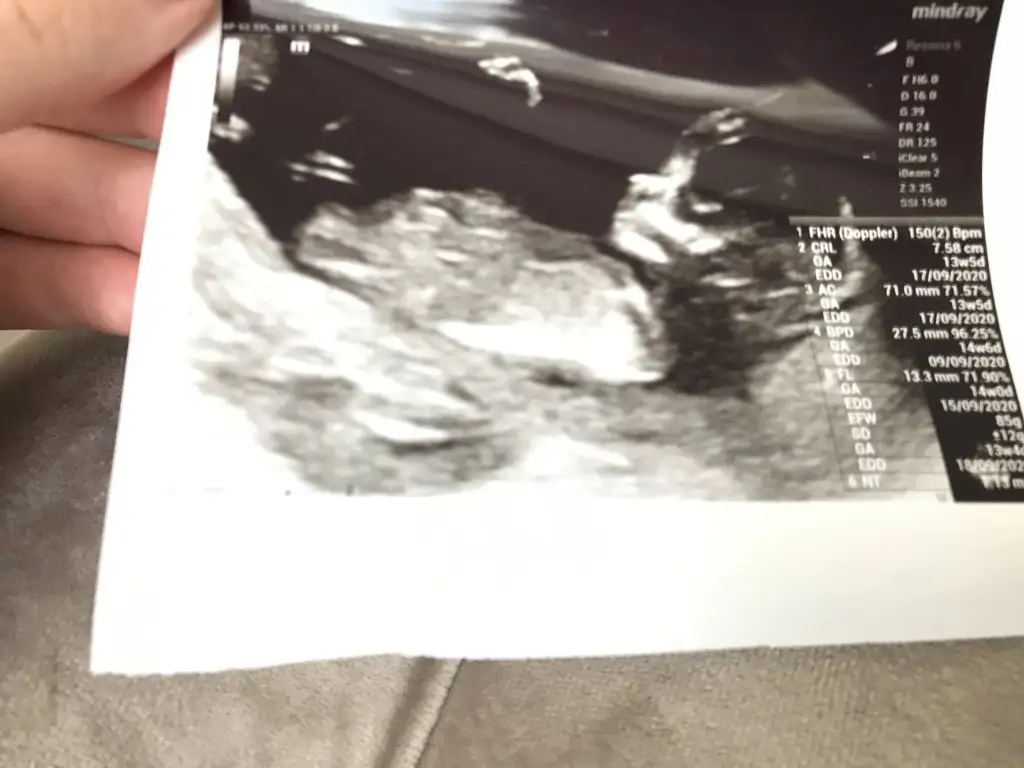

Sevgili @ıkrameyra cinsiyet tahmini alabilir miyim 🌹💕

BDA5C7BD-3496-4BB1-A970-938708FDFC4E.jpeg

Eklentiler

• 61A9F4EF-9683-43B4-B5BD-00CCB355CF56.webp

61A9F4EF-9683-43B4-B5BD-00CCB355CF56.webp

28,5 KB · Görüntüleme: 40

• C8D7EF01-26BB-4FC3-99CF-7FA7C7BDCC8C.webp

C8D7EF01-26BB-4FC3-99CF-7FA7C7BDCC8C.webp

37,8 KB · Görüntüleme: 49